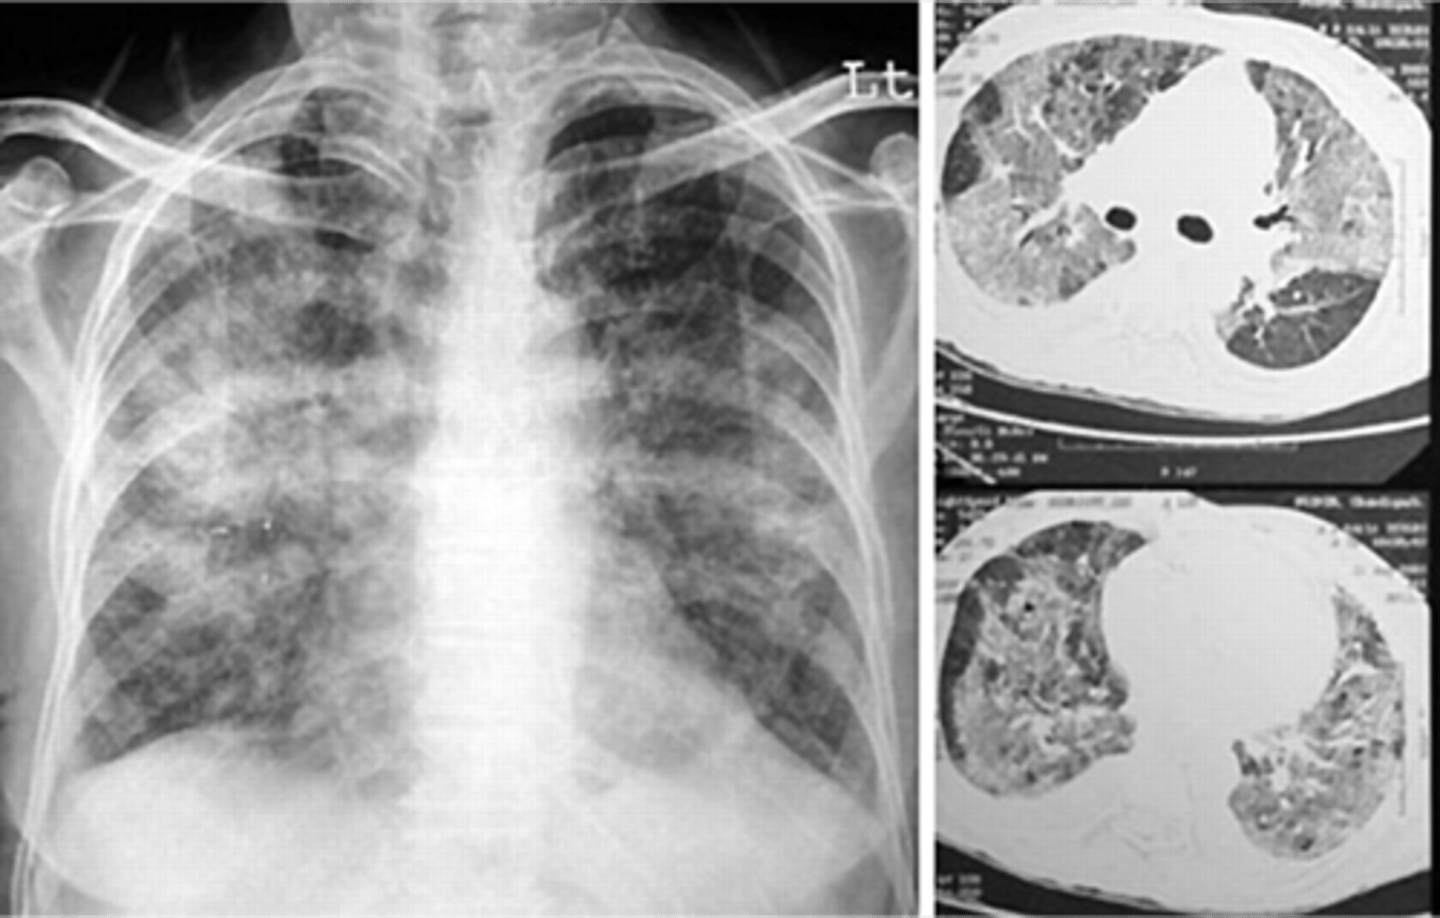

Lung cancer- adenocarcinoma

Lung cancer- squamous cell carcinoma

Lung cancer- non small cell carcinoma

Lung cancer- metastatic disease

squamous cell carcinoma

Multiple nodules- metastatic